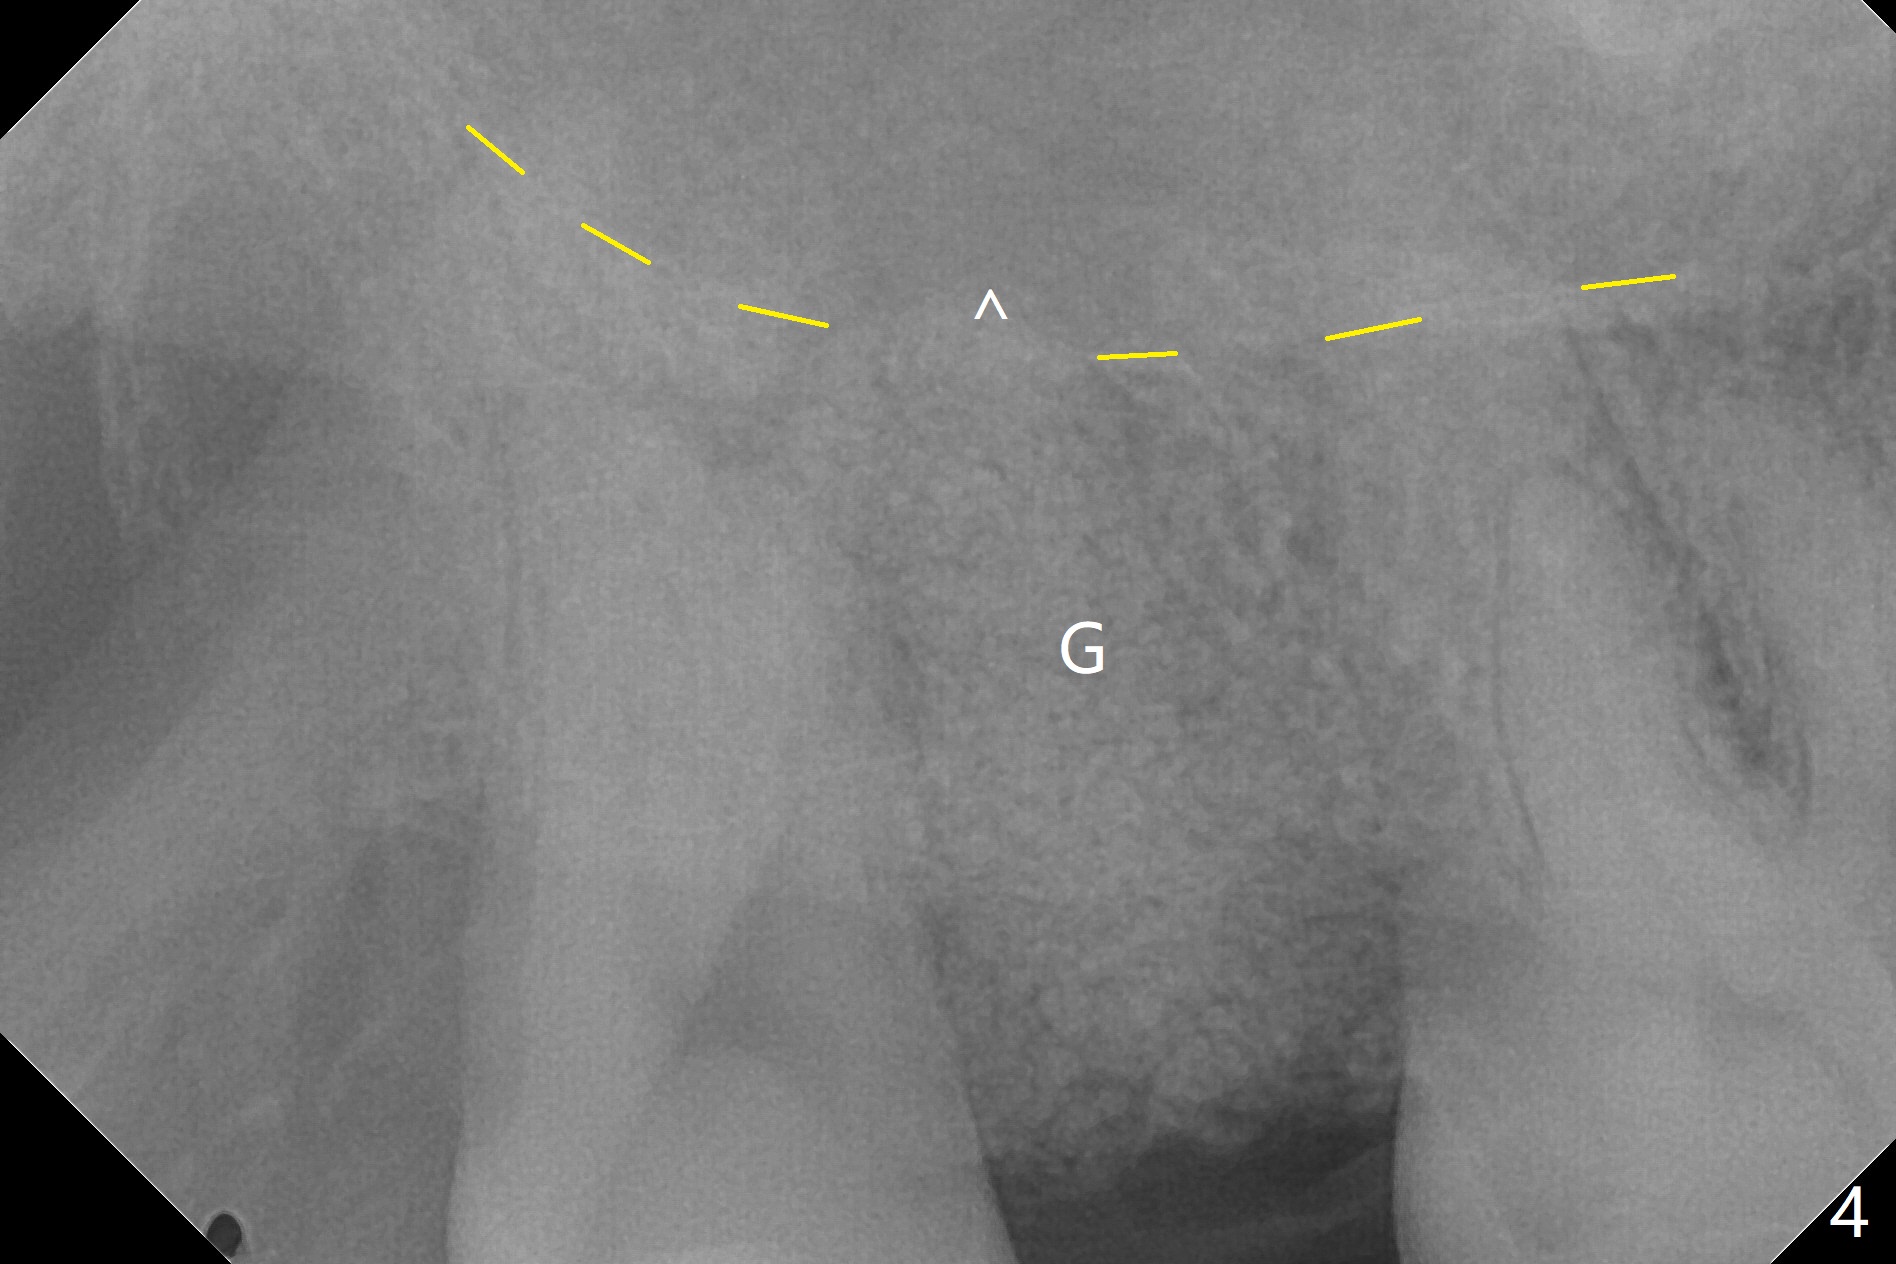

A 62-year-old man has palatal abscess with deep pockets (Fig.1 A) at tooth #2 with DO caries (Fig.2 C). The patient agrees with extraction and bone graft. Preop CT shows the palatal (P) wall defect and buccal (B) socket perforation (Fig.3 *). It should be easy to do sinus lift with the thick sinus membrane (M). To maximize hard tissue regeneration, GEM21S is used to hydrate ground cortical chips (particle size: 125μm – 850μm)) and cortical/cancellous allograft (.5-1 mm) for socket preservation (Fig.4 G) and sinus lift in the buccal socket (^). Due to swollen soft tissue and overpacking, the bone height increases (Fig.5 arrow). The socket opening is closed with GEM Cap and Perio Glue as well as perio dressing.